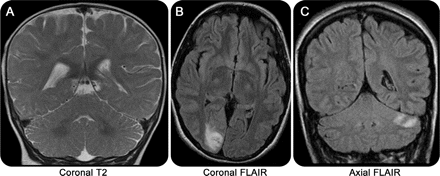

进步枕和丘脑核磁共振成像病变,包括增加皮质diffusion-weighted MRI信号强度,通常观察到的早发性和青少年Alpers。18,20.,21增加信号强度在小脑也很常见。MRI异常可以发现造成可以迅速进步,18,22,23但是MRI也可以是正常的(图3A)。灰质神经元损失与活性astrocytosis Alpers综合症的病理相关。15

(一)正常冠状T2图像的10个月大的婴儿Alpers综合症。(B)轴向fluid-attenuated反转恢复(天赋)的一名15岁女孩肌病,认知能力下降,癫痫,共济失调显示左枕叶梗死。19岁的女人(C)冠天赋与药物抗癫痫和类似中风事件显示了左小脑梗塞。POLG =γ-catalytic线粒体DNA聚合酶亚基。

成像结果变量。MRI异常包括广义脑萎缩、选择性小脑萎缩,与枕叶和多焦点的T2信号异常偏爱(图3B)。